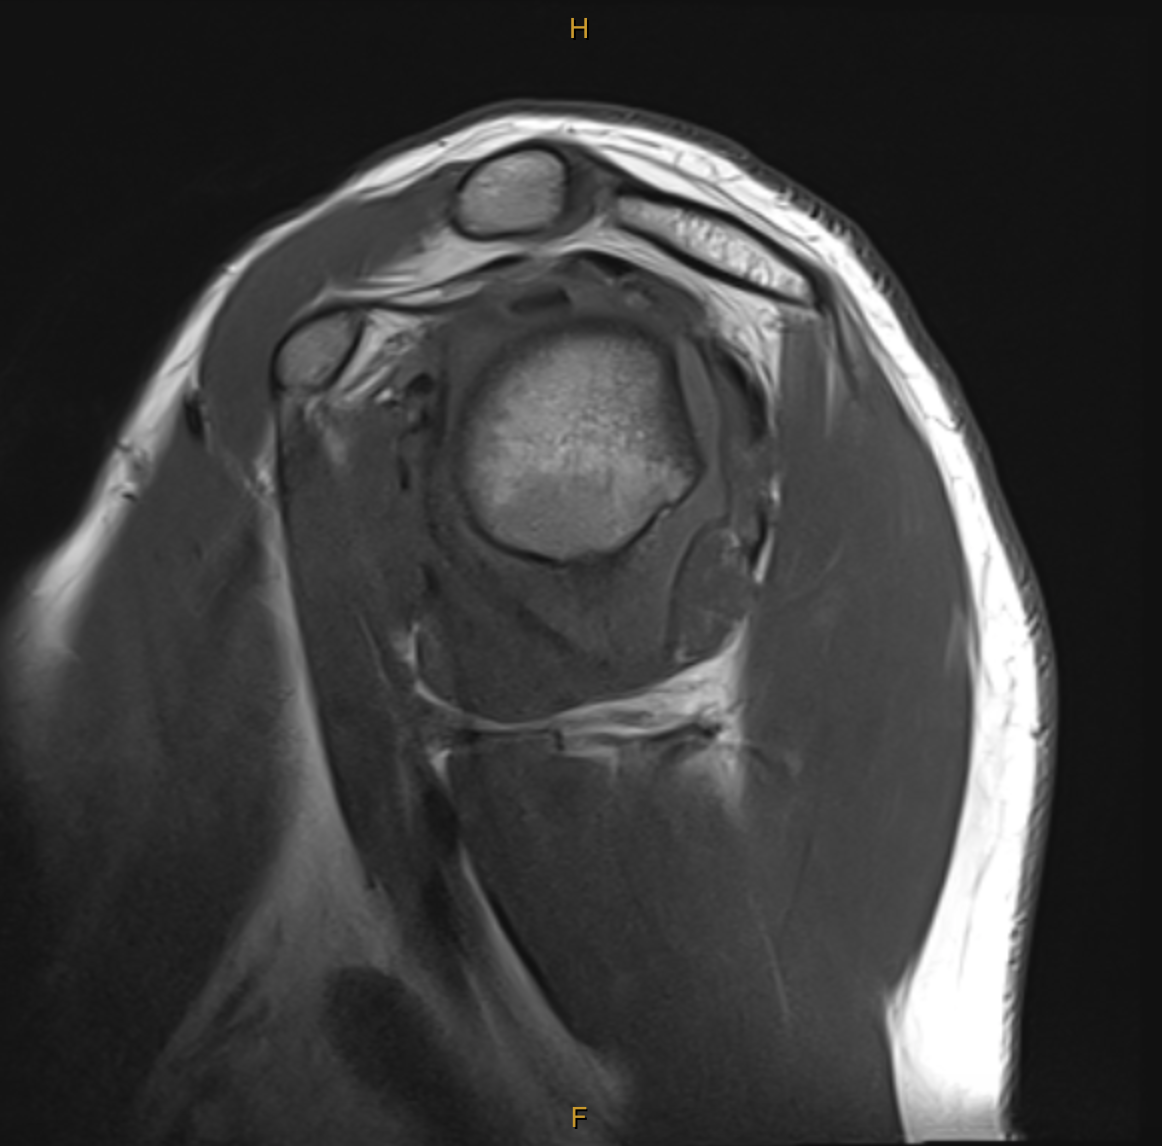

My clinical impression was the Ms C’s presentation was consistent with the event of an anterior dislocation and that MRI would best visualise the extent of tissue pathology. The report was incredibly detailed, and yet, there was additional structural damage which was not found until months later during surgery. The key findings (and my thoughts on their significance) are below:

Broad Hill-sachs lesion with underlying bone marrow oedema in keeping with recent anterior macroinstability event.

Impact fracture of the humeral head from contact on the glenoid. This fracture and indentation into the humeral head does not improve unless operated on and can lead to further instability and dislocation in positions of elevation and external rotation as the humeral head moves past the glenoid. This particular part of the injury is what is managed with the “remplissage” technique. (indication for surgery).

The bone marrow oedema can take between 3-6 months to settle (indication for wait and see).

Mild complex tear of the inferior to anterosuperior labrum extending from roughly the 6 o’clock position to the 10 o’clock position. [Fibrocartilaginous Bankart lesion]

No accompanying osseous Bankart lesion. [The glenoid was not fractured during dislocation]

There is slight elevation of the anterior glenolabral periosteum, consistent with some periosteal stripping.

No significant glenohumeral chondropathy.

Small joint effusion.

Intact cuff.

Not reported until surgery:Posterior labral tear and anteriorinferior chondral damage.

In addition to the exact MRI findings for this case, I have also added some images which outline the variants of a Bankart lesion and Hill-Sachs lesion below.